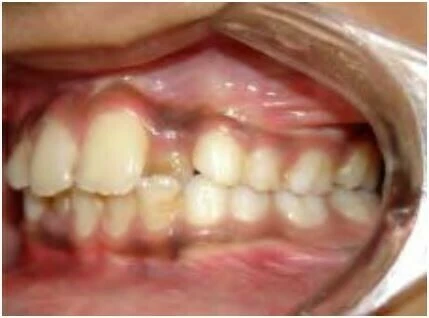

2.1 SAI KHỚP CẮN THEO MẶT PHẲNG ĐỨNG DỌC

Trường hợp này có thể được chia thành hai phân loại:

Khớp cắn nằm về phía trước so với bình thường

Với loại này, khi các răng gặp nhau tại khớp cắn trung tâm thì cung răng hàm dưới nằm về phía trước hơn.

Khớp cắn nằm về phía sau so với bình thường

Ở đây, khi các răng gặp nhau tại khớp cắn trung tâm thì cung răng hàm dưới nằm về phía sau hơn.

2.3 SAI KHỚP CẮN THEO MẶT PHẲNG NGANG

Trường hợp này bao gồm nhiều kiểu cắn chéo khác nhau. Thông thường các răng hàm trên nằm về phía ngoài so với các răng hàm dưới, nhưng đôi khi do cung răng hẹp hoặc vì một số lý do khác mà tương quan này bị xáo trộn. Chẳng hạn một hoặc nhiều răng hàm trên nằm về phía trong so với các răng hàm dưới, tình trạng này khác nhau về mức độ, vị trí và số lượng răng liên quan.